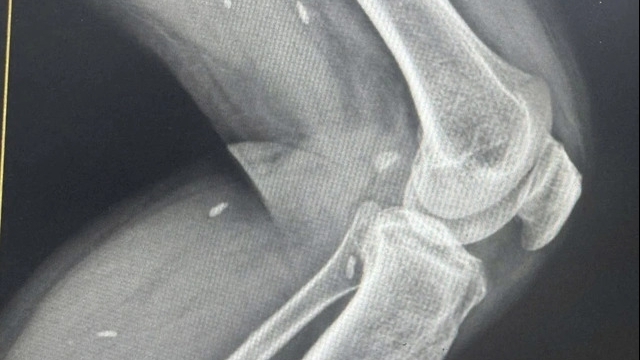

| Hình ảnh chiếc tăm dài gần 7 cm được gắp ra từ đại tràng bệnh nhân |

Bác sĩ chuyên khoa II Đặng Thành Đông, Phó trưởng khoa Ngoại tổng hợp của Bệnh viện Giao thông Vận tải cho biết: "Kiểm tra trong mổ chúng tôi thấy nguyên nhân gây viêm phúc mạc do đại tràng bị đâm thủng bởi một chiếc tăm tre còn nguyên dài khoảng 6,5cm. Các bác sĩ đã tiến hành lấy dị vật, làm sạch và khâu lỗ thủng đại tràng.